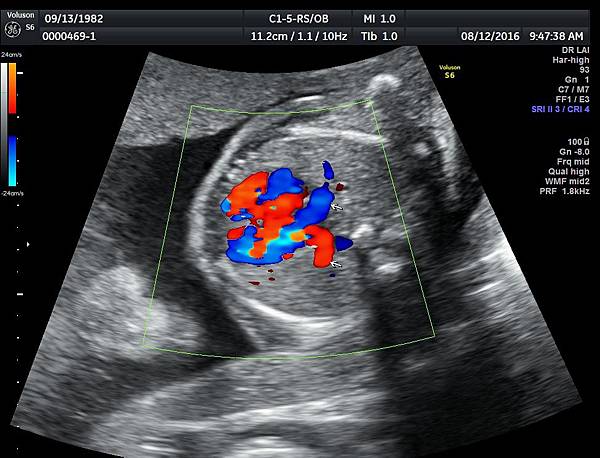

我看肺靜脈的心路歷程可以分成三個階段,第一個階段是用gray scale(黑白)看到左右肺靜脈下行支回到左心房(附圖 1.2.),第二個階段是用flow(彩色)看到左右肺靜脈回到左心房(附圖 3.4.),第三階段是同時要看到黑白和彩色的左右肺靜脈回到左心房,為什麼只有看flow(彩色)不安全呢?因為右肺靜脈的flow有時候是假影,為何會看到假影?因為右心房到左心房的flow overlapping(重疊)造成的(附圖 5.),如何判斷是假影,只要關掉flow看黑白的即可證明右肺靜脈沒有進入左心房(附圖 6.)。

如果同時看到左右肺靜脈進入左心房,這種誤判的機率下降很多,如果只能看到一條肺靜脈的血流,我會選擇左肺靜脈(附圖 7.8.),因為左肺靜脈的血流比較不會被overlapping,最安全的方法是黑白和彩色都看到左右肺靜脈進入左心房,只是需要胎兒姿勢配合,當然孕婦的體重也是需要考量的因素。